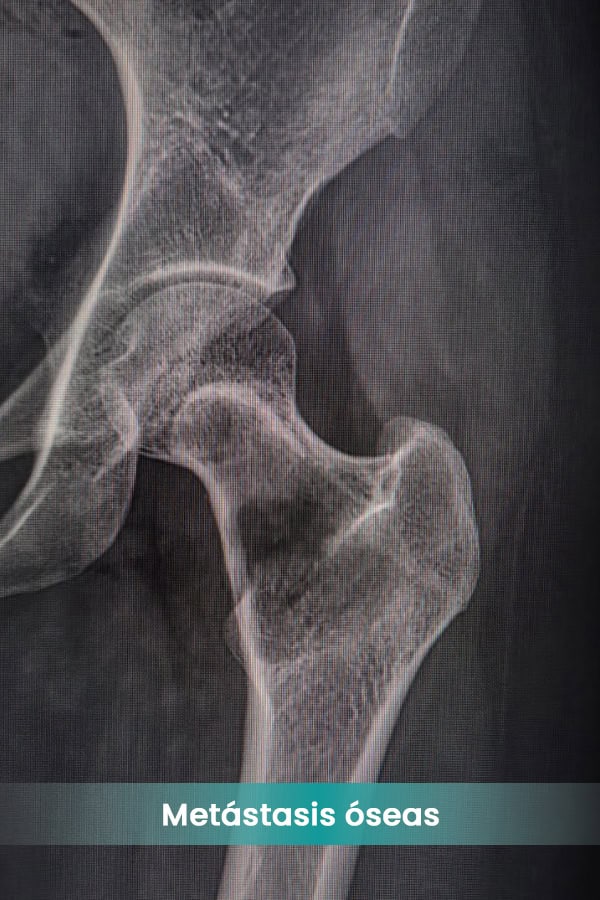

óseas

- Mieloma múltiple

- Cáncer de mama

- Cáncer de próstata

- Cáncer de pulmón

- Cáncer renal

- Cáncer de tiroides

- Cáncer de colon

- Cáncer gástrico